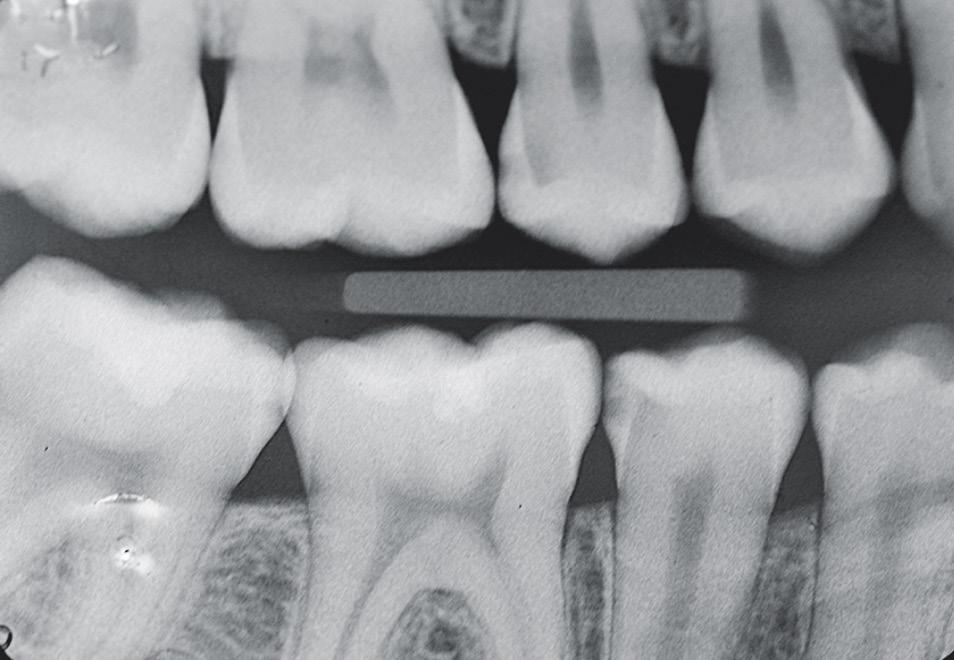

Fig. 1: Radiograph of initial situation: second upper premolar with deep carious lesion close to pulp. Fig. 2: Preop: intact occlusal surface of the second premolar, carious lesion was visible on radiograph. Fig. 3: Insertion of a proximal wedge. Fig. 4: Customization of sectional matrix clamp.